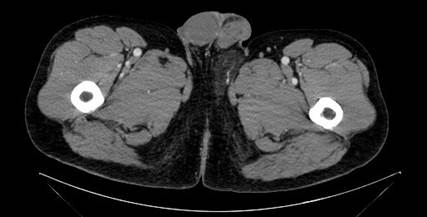

Una tomografía computarizada (TC) abdominopélvica con contraste mostró una lesión sólida de 6,1 cm de diámetro anteroposterior x 3 cm de diámetro transverso de densidad grasa, ligeramente más hiperdensa que la circundante con vascularización en su interior. (Figura 1)

Figura 1 TC. Lesión sólida de 6x3 cm de densidad grasa más hiperdensa que el tejido adiposo circundante.